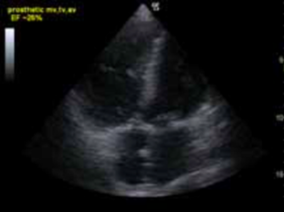

What does this patient have?

Pericardial effusion, note the fluid going around the heart